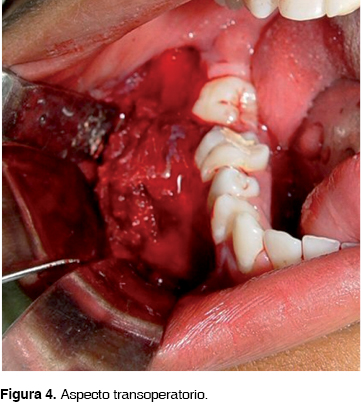

Bajo anestesia general e intubación nasotraqueal, se diseñó una incisión contorneante con extensión distal retromolar y liberatriz vestibular anterior, levantamiento de colgajo mucoperióstico, curetaje completo de la lesión, extracciones de los dientes involucrados y fresado quirúrgico de los bordes, conservando el nervio alveolar inferior el cual se encontraba desplazado (Figura 4). Posterior a la reposición de colgajo mucoperióstico, se suturó con material reabsorbible, previa colocación de esponja hemostática en el espacio muerto.